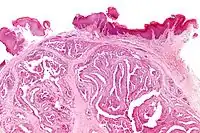

Microscopic histopathological analyses of papillary hidradenoma tumors typically reveal a nodule in the dermis, i.e. layer of skin between the epidermis and subcutaneous tissue. The tumor consists of complex patterns of interconnecting tubular and papillary (i.e. thin finger-like or frond-like) structures.[20] These structures are lined with glandular epithelial and myoepithelial cells. The glandular epithelial cells appear to be excessively proliferating in the ducts leading to the epidermis and show oxyphilic changes, (i.e. cytoplasm filled with large mitochondria, glycogen, and ribosomes) while the myoepithelial cells often appear clear cell-like, i.e. have uncolored cytoplasm when stained with hematoxylin and eosin.[1] The histopathology of anogenital and ectopic papillary hidradenomas are similar to each other.[7][9][15][18]

Micrograph of a papillary hidradenoma with the characteristic papillary structures and epithelium with apocrine snouts. A fragmented overlying epidermis is seen at the top of the image. H&E stain. -

a,b) Cells of lumina showed decapitation secretion similar to apocrine gland -

Intermed. mag. -

Very high mag.